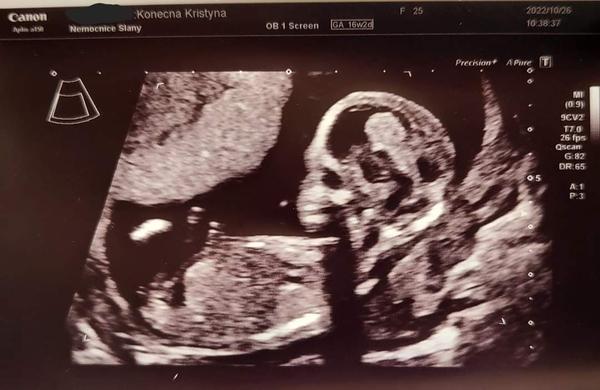

tento týden začínám 15 tt a už jsem byla na prvním screeningu, všechno bylo v pořádku a mám krásnou fotečku miminka.

Jenže co mě zajímá je pohlaví, ještě mi ho neřekli protože je to 50/50 ale už jsem strašně nedočkavá. Na druhý screening jdu až polovině prosince což je až za měsíc a něco a tam mi to prý už na 100% řeknou jenže pro mě to je nekonečná doba 🙂 Moc bych si přála chlapečka a partner taky, protože doma už dvě holky máme ale jsou to moje nevlastní. Přikládám foto co myslíte?

Holčička